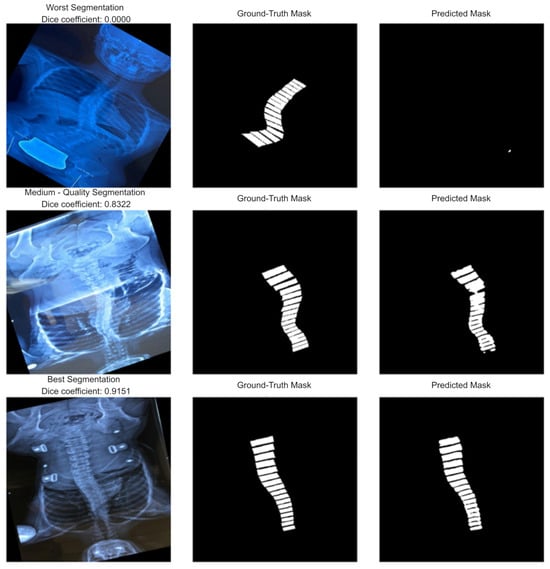

Figure 8 illustrates qualitative segmentation results of the U-Net model during testing, highlighting 3 different performance levels:

Figure 8.

Examples of worst (top row)/medium (middle row)/best (bottom row) segmentations.

Worst Segmentation (top row, Dice = 0.0000): The predicted mask fails to capture the vertebral structure entirely, resulting in no meaningful overlap with the ground truth. This case represents a complete failure of the segmentation process, possibly due to poor image quality, extreme anatomical variation, or noise.

Medium-Quality Segmentation (middle row, Dice = 0.8322): The predicted mask aligns reasonably well with the ground truth but shows minor inaccuracies in boundary definition and continuity. While the vertebral column is mostly identified, some misalignments and partial omissions reduce accuracy.

Best Segmentation (bottom row, Dice = 0.9151): The predicted mask closely matches the ground truth with minimal deviation. The vertebral boundaries are well preserved, and segmentation quality is high, reflecting strong model performance on this sample.

In addition to quantitative evaluations such as Dice score and precision–recall analysis, qualitative examples illustrate the performance variability of the U-Net model. Representative cases from the test set, corresponding to the worst, medium, and best segmentation outcomes, demonstrate how the model performs under different conditions. These visual results highlight both the strengths of the model, where the predicted masks closely align with the ground truth, and its limitations, where segmentation accuracy deteriorates due to challenging image characteristics. Such qualitative analysis provides an essential complement to numerical metrics, offering deeper insights into the practical reliability and interpretability of the model in real-world applications.